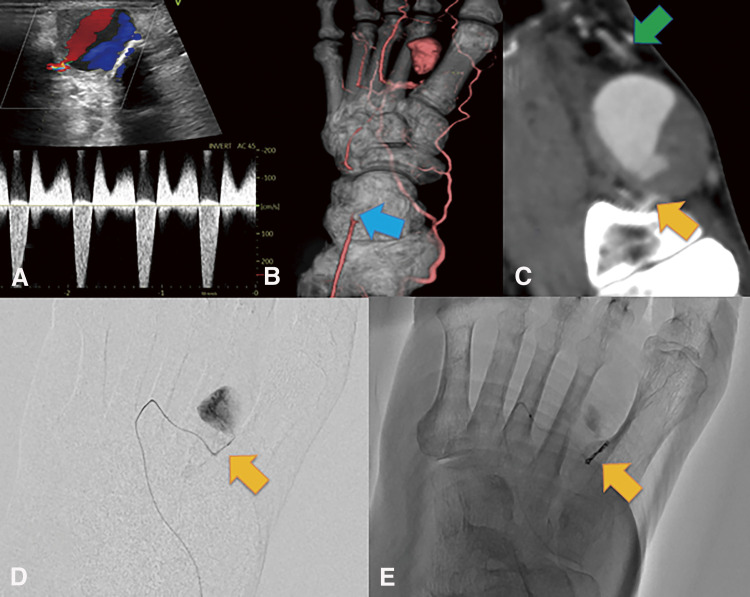

Case presentation: A 76-year-old man with no history of foot trauma presented with pain and a pounding mass in the dorsum of the left foot. Echography revealed a 29 × 18 × 20 mm saccular aneurysm with to-and-fro blood flow. Contrast-enhanced computed tomography revealed an aneurysm in the first dorsal metatarsal artery. Angiography of the aneurysm revealed no arterial drainage. Embolization was subsequently performed only for the feeding artery, which was the proximal first dorsal metatarsal artery, using the 2 Target nanocoils (Stryker; Boston, MA, USA), resulting in successful occlusion. However, echography performed a few months after embolization revealed a recurrence of blood flow and enlargement of the coiled aneurysm. Nine months after embolization, the pain in the dorsum of the foot recurred. Therefore, we performed a surgical resection of the dorsal metatarsal artery aneurysm (38 × 26 × 26 mm) under general anesthesia. The first distal dorsal metatarsal artery exhibited pulsatile bleeding, and angiography of the distal dorsal metatarsal artery revealed a patent pedal arch and posterior tibial artery. Therefore, revascularization was not performed. The postoperative course was uneventful. The pathological examination indicated that the mass was a pseudoaneurysm.